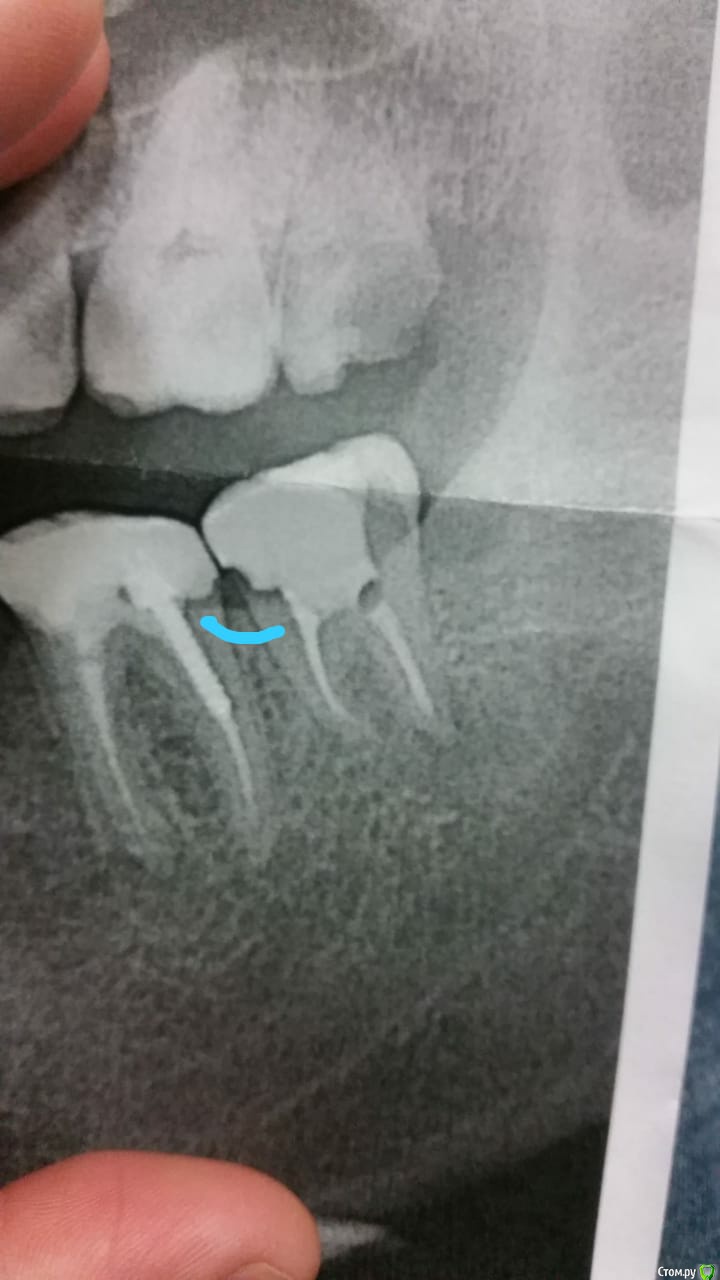

John_P Опубликовано 13 ноября, 2018 Поделиться Опубликовано 13 ноября, 2018 (изменено) Здравствуйте! Подскажите что делать. Пару недель назад сделали два зуба нижних (17-18) и удалили восьмерку верхнюю (16). Начал болеть сильно 18-й запломбированный зуб, хотя в нем нервы удалены. Болит когда по нему стучишь или ешь им. Пришел к врачу на прием, сказала что это пища забивается между зубов, нужно чистить ниткой и полоскать содой и что болит это десна а не зуб. Сделал снимок в другой клиники и врач сказал что зуб сделан не совсем правильно и его надо переделывать, потому что есть между зубов выпуклость где постоянно будет забиваться еда и вода и он скоро испортиться. И еще не понятно что со вторым корнем, который не просвечивается рентгеном. Снимок в приложении. Зуб болит дело в нем или нет не пойму. Подскажите что делать? Изменено 13 ноября, 2018 пользователем John_P Ссылка на комментарий

kramer Опубликовано 13 ноября, 2018 Поделиться Опубликовано 13 ноября, 2018 (изменено) Вы случайно не из США? В зубе 37 воспалительные очаги у корней, которые и дают боль. Либо перелечивать каналы в зубе, либо удалять зуб Изменено 13 ноября, 2018 пользователем kramer Ссылка на комментарий